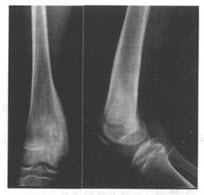

患儿,男,16岁。因右下肢酸痛、行走后加重2个月入院;查体:右股骨下端软组织稍肿,干骺端轻压痛。无全身症状,实验室血尿常规检查无异常发现。

第1题,共3个问题

(单选题)为了进一步诊断,你认为首先需要做哪些检查()

A:X线平片

B:CT

C:MRI

D:放射性核素扫描

E:B超检查

F:血沉

第2题,共3个问题

(单选题)患者左股骨中下段正侧位平片如图,你认为最可能的诊断是什么()

A:慢性骨髓炎

B:疲劳骨折

C:内生软骨瘤

D:骨结核

E:骨母细胞瘤

F:骨样骨瘤

第3题,共3个问题

(多选题)下列哪几项符合该种疾病的诊断()

A:发病年龄多小于30岁

B:患骨疼痛为主

C:疼痛夜间加重

D:起病较快,病程较短

E:多发生于长管状骨

F:服用水杨酸性药物可缓解疼痛